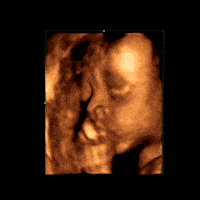

▶监测胎宝宝的生长发育

检测胎宝宝发育是根据测量胎宝宝各部门的数值来判断的,如胎头双顶径等。

▶胎宝宝是否畸形

四维彩超检查是发现胎儿畸形的一个重要手段。一旦发现胎儿畸形,就可以及时终止妊娠!